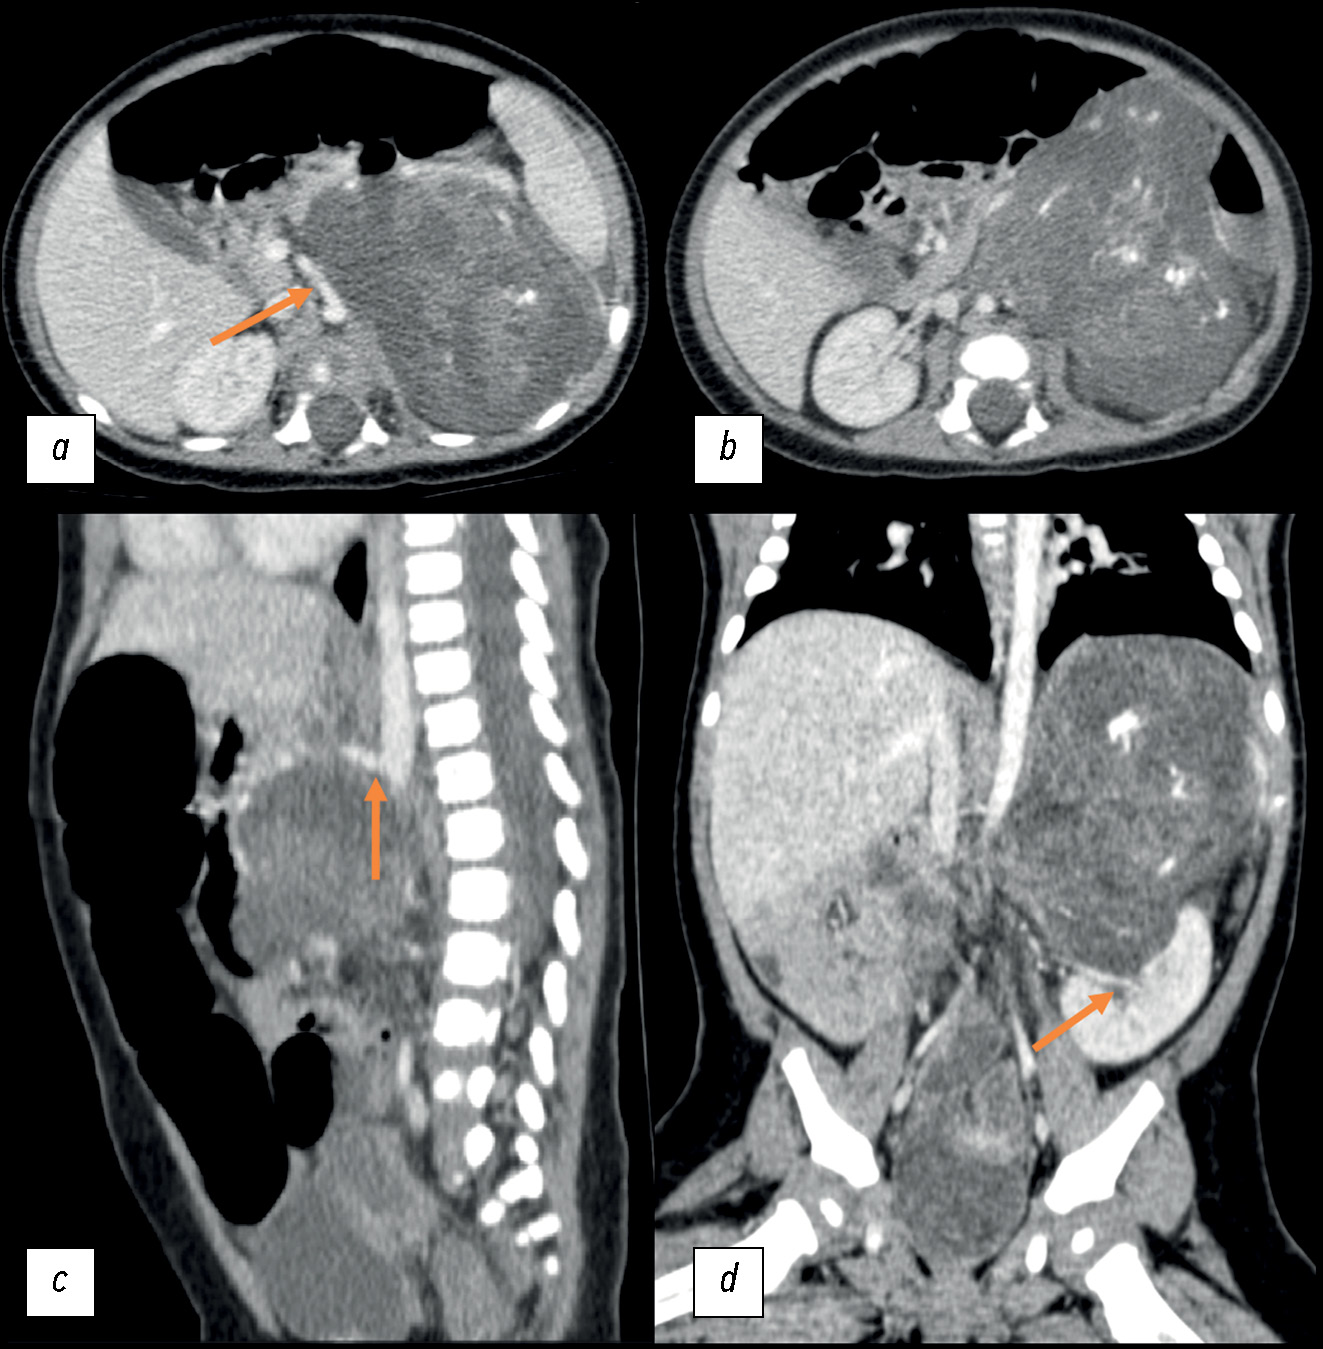

The most common adrenal tumor in young children is neuroblastoma, which can be difficult to differentiate from other conditions such as nephroblastoma, adrenal hemorrhage, angiomyolipoma, myelolipoma, and adenoma. This article describes a case of teratoma, one of the rarest adrenal tumors in children. Initially, despite its large size, it demonstrated all the radiological and histological signs of neuroblastoma. Teratomas are germ cell tumors usually found in the gonads. Adrenal teratomas are extremely rare, accounting for approximately 0.13% of all adrenal tumors. Typically, adrenal teratomas are asymptomatic, as the retroperitoneal space is large enough to accommodate the growth of the tumor without causing symptoms. For the first time in domestic literature, we present a clinical case of adrenal teratoma in a 3-month-old child. The article also presents a detailed description of the diagnostic process and challenges that radiologists and clinicians face when encountering a common tumor in a very rare location for children. This report aimed to help physicians increase awareness of this rare condition and include adrenal teratomas in the potential differential diagnosis of adrenal neoplasms.